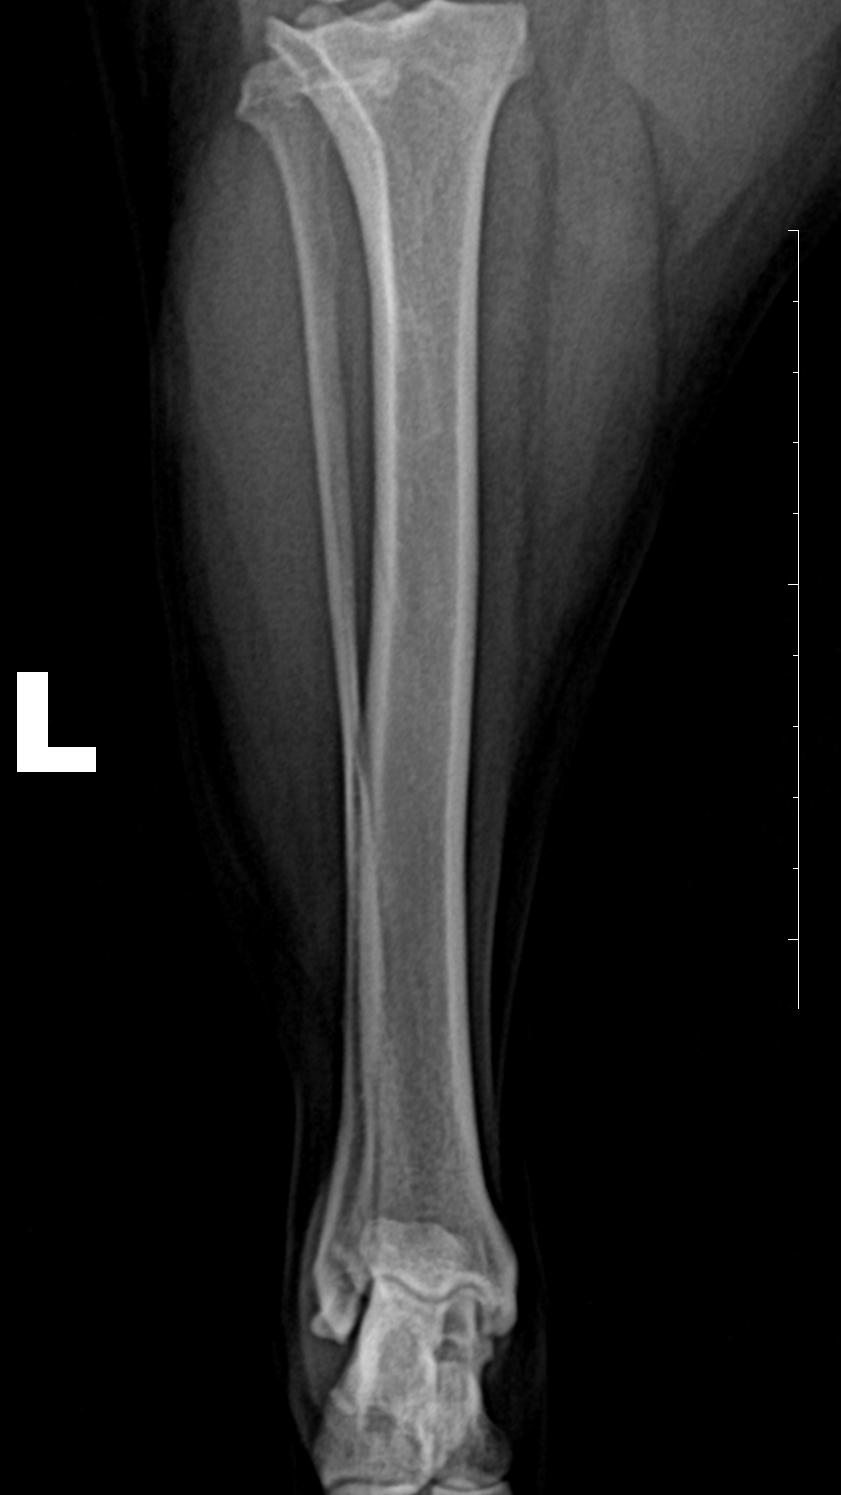

DR检查

右后肢股骨滑车脊的关节周围有新骨生成。

左、右后肢侧位 片 关节腔内软组织不透明度增加,膑下脂肪垫向前位移;

左后肢前后位↑

左后肢内外位↑

正位片可见关节内侧软组织不透明度增加;胫骨粗隆前移。